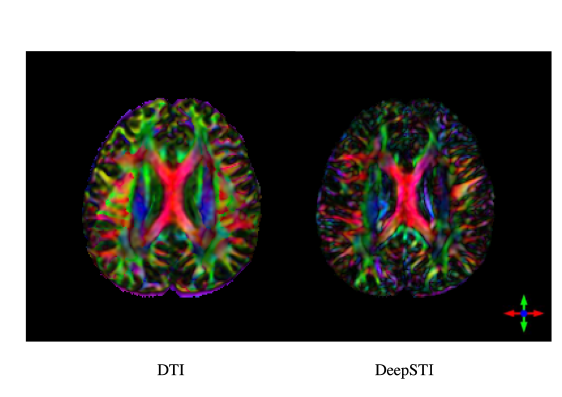

Refer to caption

Figure 1: Anisotropy weighted principal eigenvector (PEV) maps estimated from real measurements from a human subject. Left: fractional anisotropy (FA) weighted DTI PEV map acquired at 3T and 2.2 mm isotropic resolution (interpolated to 0.98×\times0.98×\times1 mm resolution). Right: magnetic susceptibility anisotropy (MSA) weighted STI PEV map estimated by DeepSTI from 4 GRE measurements at 7T acquired at 1 mm isotropic resolution (reconstructed to 0.98×\times0.98×\times1 mm resolution). The acquisition time for STI was 21 minutes (4 head orientations, 5 minutes 15 seconds per orientation). The acquisition time of DTI was 8 minutes 50 seconds.

In this paper, we present an approach towards solving the above issues by developing new machine learning based methods for STI image reconstruction that allow for a reduced number of head orientations. Specifically, we developed a STI algorithm, called DeepSTI, that approximately minimizes a regularized STI reconstruction problem, where the regularization is based on a prior that is learned from data. To this end, we leveraged advances in deep learning methods, which have recently demonstrated encouraging results in solving ill-posed inverse problems in medical imaging but have not yet been applied for the challenging problem of STI reconstruction, potentially due to its high-dimensional nature and the difficulty to incorporate MR phase measures acquired at varying number of orientations and arbitrary angles as input. Here, we exploited the learned proximal convolutional neural network (LPCNN) model, used previously for reconstructing isotropic magnetic susceptibility sources as in quantitative susceptibility mapping (QSM) [36], and we expanded it to bear in the context of this more challenging task of STI. We validated our method using simulations as well as applied it on in vivo human data, and compared it to existing state-of-the-art STI reconstruction methods. The proposed algorithm shows unprecedented results for STI reconstruction with fewer than 6 orientations, with superior performance over previous methods in the reconstruction of tensor image and principal eigenvector (PEV) maps. DeepSTI also produces more coherent results in fiber tractography from STI, and is not limited to using uniform resolution across samples. Figure 1 depicts an example result, demonstrating the improved resolution of STI over that of DTI, on a human subject.